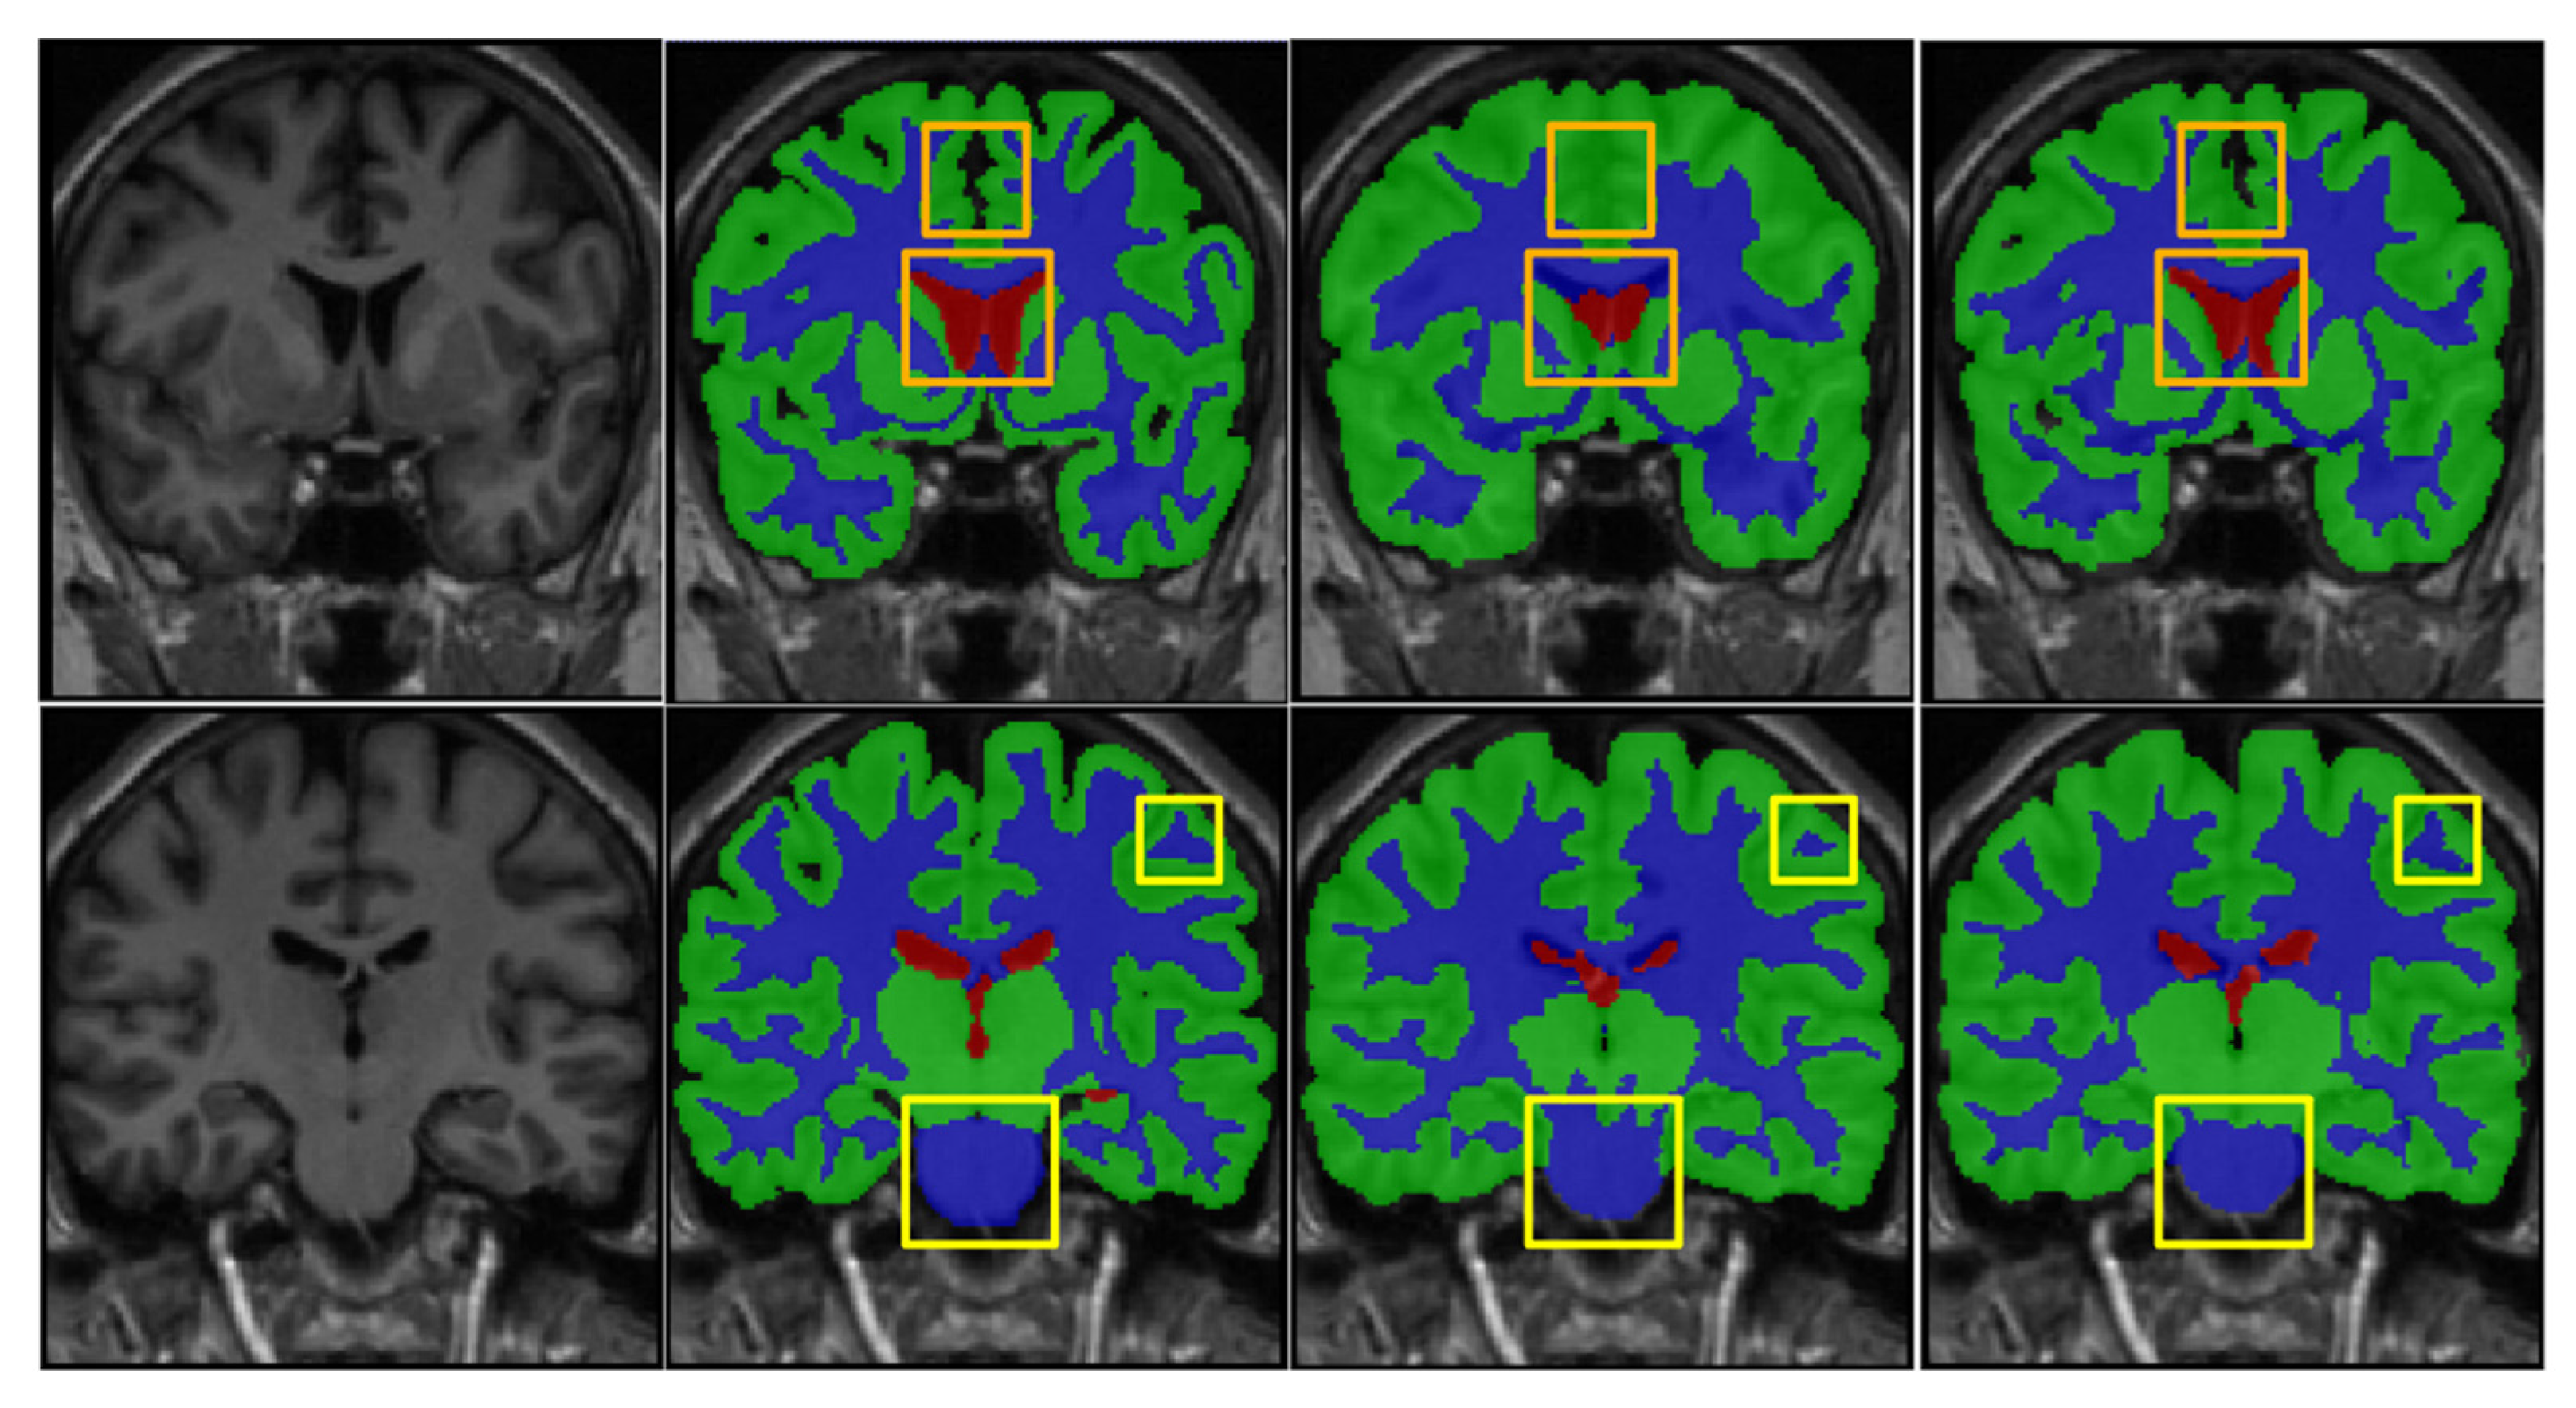

4. Results

4.3. Comparison with Existing State-of-the-Art Methods